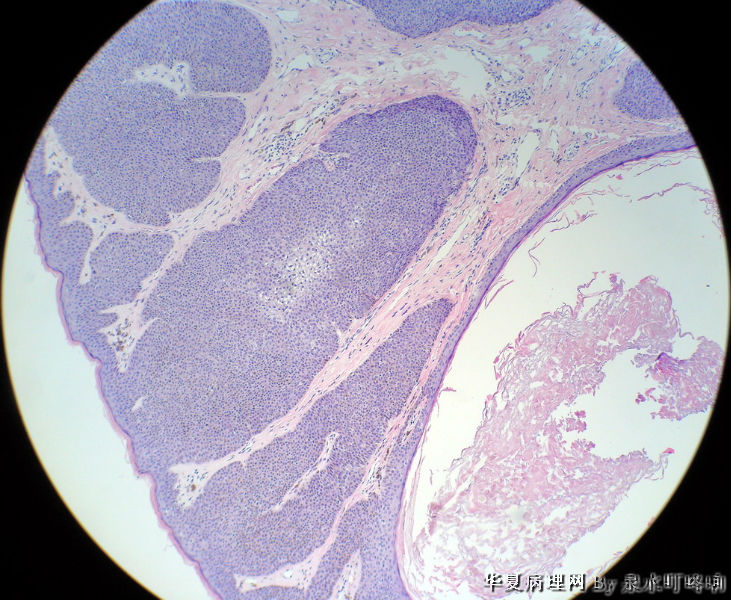

左耳后肿物

男,80岁,左耳后肿物十余年。左耳后肿物图1

棘层肥厚型脂溢性角化症

脂溢性角化病

同意脂溢性角化病,该例主要需要和汗孔瘤鉴别。

毛发上皮瘤

典型的棘层肥厚型脂溢性角化症!